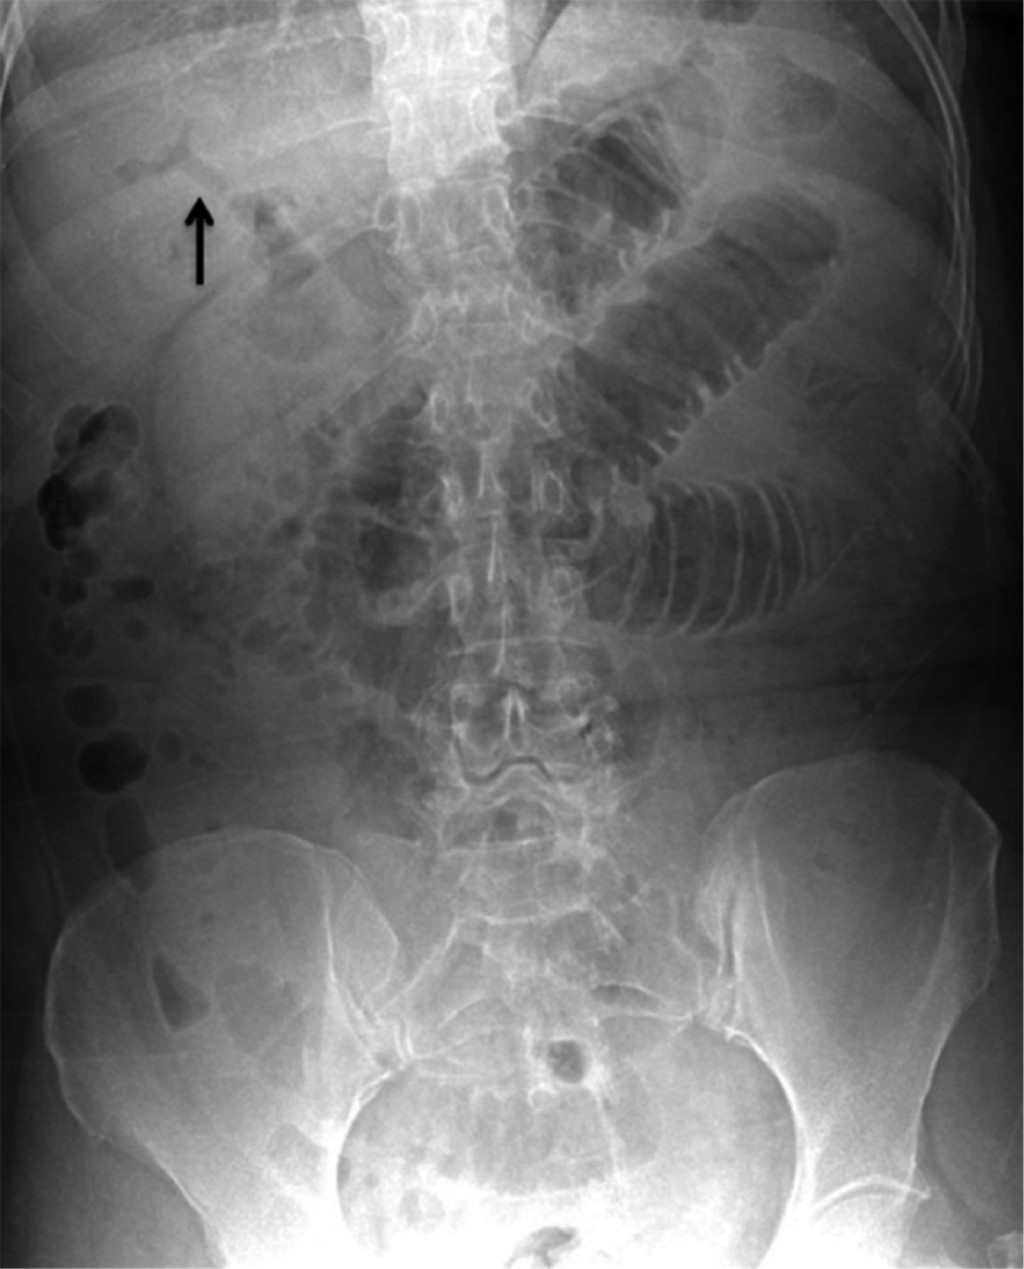

Paciente femenino de 59 años de edad con antecedente de evento vascular cerebral isquémico hace cinco años, diabetes tipo 2 en control con hipoglucemiantes orales (metformina de 850 mg cada 12 horas y glibenclamida de 5 mg cada 24 horas), hernia hiatal sin cirugía y cardiopatía isquémica en control con ácido acetilsalicílico de 100 mg vía oral cada 24 horas y atorvastatina de 40 mg vía oral cada 24 horas. Su padecimiento inicia con náuseas y vómito de contenido gastrointestinal color café, que conduce a intolerancia a la vía oral acompañada de dolor en epigastrio referido en intensidad 7/10, automedicada con antiespasmódicos y antiinflamatorios no esteroideos (AINE), con mejoría parcial; 48 horas posteriores al inicio de los síntomas, incrementa la intensidad del dolor y presenta distensión abdominal, así como incapacidad de canalizar gases por recto. A su ingreso al servicio de urgencias, la paciente se encontró deshidratada, con abdomen distendido, doloroso a la palpación superficial y ruidos metálicos. Se colocó sonda nasogástrica cuyo gasto fue fecaloide. Bioquímicamente con falla renal aguda, desequilibrio hidroelectrolítico y acidosis metabólica. Radiográficamente con asas de intestino delgado dilatadas, neumobilia (Figura 1) y datos de oclusión intestinal. Ante esto, se decide exploración quirúrgica laparoscópica, observándose dilatación de asas de intestino delgado hasta un segmento de íleon, localizado a 150 cm de válvula ileocecal, donde se observa una protuberancia que marca el fin de la dilatación intestinal y que corresponde a un lito de 3.5 cm enclavado; se realiza enterotomía, extracción de lito y cierre primario en un plano, sutura continua con prolene 2-0 (Figura 2). En el transoperatorio, la paciente se comportó con inestabilidad hemodinámica, por lo que fue necesario iniciar apoyo con norepinefrina (16 mg en 250 ml de solución salina al 0.9%) a 8 ml/h, dosis, que fue en descenso hasta su retiro total en 48 horas. Posteriormente, evolucionó de manera favorable, siendo egresada al quinto día manteniendo estabilidad hemodinámica, tolerando la vía oral, sin datos de respuesta inflamatoria sistémica. Actualmente, a un año de la cirugía, continúa en seguimiento por consulta externa como paciente ambulatoria sin haber presentado complicaciones relacionadas al evento quirúrgico.

Los hallazgos radiográficos en una proyección simple de abdomen incluyen: neumobilia, datos de obstrucción intestinal, una imagen sugestiva de lito en asas intestinales y cambios en localización de un lito visualizado en una radiografía previa.9-13 El uso de la tomografía es un importante apoyo diagnóstico; se ha reportado una sensibilidad, especificidad y precisión diagnóstica de 93, 100 y 99%, respectivamente.13 El tratamiento inicial es la reanimación hídrica, ya que estos pacientes se presentan con deshidratación. El abordaje quirúrgico laparoscópico ofrece más ventajas en comparación con la cirugía abierta, la recuperación requiere menor tiempo. Sin embargo, representa un reto técnico, y más cuando las asas intestinales se encuentran edematosas y dilatadas.14 En nuestro caso, preferimos el abordaje laparoscópico sobre el abierto por las ventajas que la cirugía de mínima invasión ofrece. La paciente no presentó complicaciones relacionadas al evento quirúrgico. Existe controversia en cuanto al manejo de la fístula bilioentérica; por un lado, se prefiere únicamente la enterotomía, extracción del lito y cierre primario y, por otro, además de lo anterior, se realiza desmantelamiento de la fístula y colecistectomía.8 Se ha reportado que los pacientes de edad avanzada y con múltiples comorbilidades representan un verdadero reto, ya que existe un incremento considerable de fugas, tanto intestinales como biliares, al realizar todos los procedimientos descritos en una sola cirugía.15 En nuestro caso, decidimos realizar únicamente enterotomía, extracción del lito y cierre primario debido a las condiciones de la paciente al momento de su ingreso a la sala de quirófano y al comportamiento de inestabilidad hemodinámica transoperatoria. Tomamos la decisión de resolver la urgencia.

Figura 1